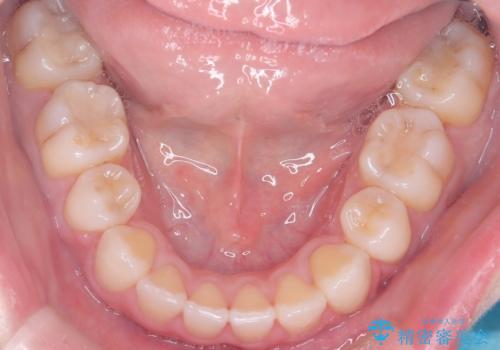

上下4本の抜歯と審美ワイヤー矯正で整った歯並びへ

- 患者様は、歯並びの乱れを整えたいとのことで来院されました。診察の結果、歯列のスペース不足が原因で前歯のガタつきが目立ち、噛み合わせにも影響が出ている状態でした。歯を正しく並べるためにはスペースの確保が必要と判断し、上下の小臼歯4本を抜歯して、審美ワイヤー矯正(白いワイヤーと透明ブラケット)で治療を行う計画を立てました。

まず、抜歯によって歯を動かすためのスペースを確保。その後、審美ワイヤー矯正を用いて、前歯のガタつきを整えながら、噛み合わせの調整も行いました。審美装置を使用することで、矯正中も目立ちにくく、自然な仕上がりを目指して治療を進めました。治療の結果、歯並びがきれいに整い、口元のバランスも改善しました。患者様からは「歯並びがきれいになり、自信を持って笑えるようになった」と喜びの声をいただきました。